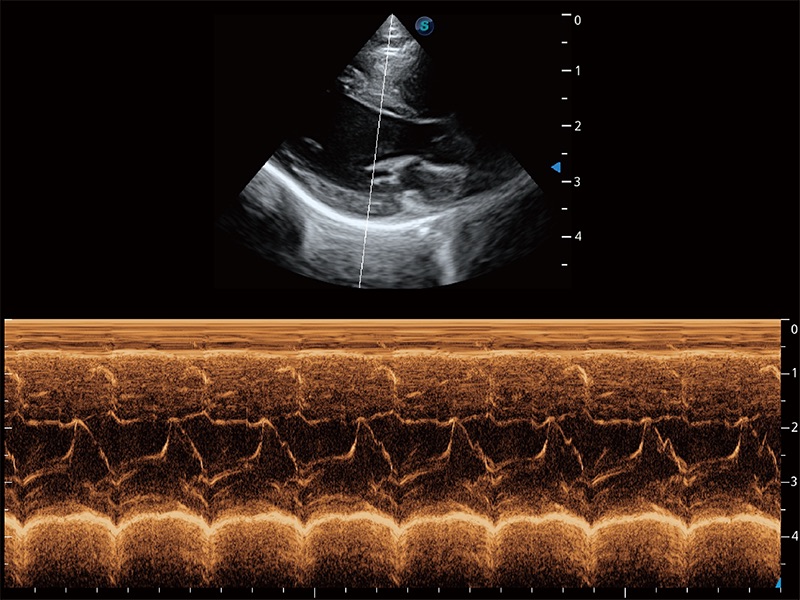

ProPet 80 配备了丰富的心脏探头群、先进的成像技术和专业的心脏测量工具,可帮助动物医生为不同体型和生理结构的动物提供心脏和心肌功能的全面评估。

通过360度任意调节3条M型取样线,在同一心动周期上观察心脏不同位置的运动曲线,得到准确的心功能测量数据,有效评估心肌运动及左心室功能。

能够增加心肌组织与血流之间的区别。对于心脏扫查困难的动物,可提供更好的心内膜边界的显示。